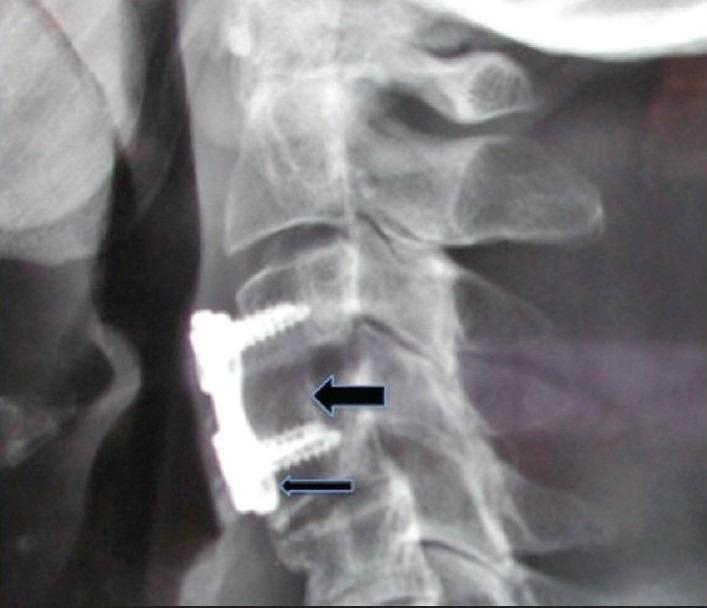

髂嵴自体骨移植与颈椎前路手术的替代植入物:利弊与成本

Iliac crest autograft versus alternative constructs for anterior cervical spine surgery: Pros, cons, and costs.

Grafting choices available for performing anterior cervical diskectomy/fusion (ACDF) procedures have become a major concern for spinal surgeons, and their institutions. The "gold standard", iliac crest autograft, may still be the best and least expensive grafting option; it deserves to be reassessed along with the pros, cons, and costs for alternative grafts/spacers.

Although single or multilevel ACDF have utilized iliac crest autograft for decades, the implant industry now offers multiple alternative grafting and spacer devices; (allografts, cages, polyether-etherketone (PEEK) amongst others). While most studies have focused on fusion rates and clinical outcomes following ACDF, few have analyzed the "value-added" of these various constructs (e.g. safety/efficacy, risks/complications, costs).

The majority of studies document 95%-100% fusion rates when iliac crest autograft is utilized to perform single level ACDF (X-ray or CT confirmed at 6-12 postoperative months). Although many allograft studies similarly quote 90%-100% fusion rates (X-ray alone confirmed at 6-12 postoperative months), a recent "post hoc analysis of data from a prospective multicenter trial" (Riew KD et. al., CSRS Abstract Dec. 2011; unpublished) revealed a much higher delayed fusion rate using allografts at one year 55.7%, 2 years 87%, and four years 92%.

Iliac crest autograft utilized for single or multilevel ACDF is associated with the highest fusion, lowest complication rates, and significantly lower costs compared with allograft, cages, PEEK, or other grafts. As spinal surgeons and institutions become more cost conscious, we will have to account for the "value added" of these increasingly expensive graft constructs.

对于脊柱外科医生及其所在机构而言,可用于颈椎前路椎间盘切除/融合术(ACDF)的移植选择已成为一个主要关注点。“金标准”——自体髂骨移植,可能仍是最佳且成本最低的移植选择;值得对其以及替代移植材料/椎间融合器的利弊和成本进行重新评估。

尽管单节段或多节段ACDF使用自体髂骨移植已有数十年,但植入物行业如今提供了多种替代移植材料和椎间融合器装置(如异体移植物、椎间融合器、聚醚醚酮(PEEK)等)。虽然大多数研究聚焦于ACDF后的融合率和临床结果,但很少有研究分析这些不同结构的“附加值”(如安全性/有效性、风险/并发症、成本)。

大多数研究表明,使用自体髂骨移植进行单节段ACDF时(术后6 - 12个月经X线或CT证实),融合率为95% - 100%。尽管许多异体移植物研究同样报出90% - 100%的融合率(仅术后6 - 12个月经X线证实),但最近一项“对一项前瞻性多中心试验数据的事后分析”(Riew KD等人,CSRS摘要,2011年12月;未发表)显示,使用异体移植物时,1年延迟融合率高达55.7%,2年为87%,4年为92%。

与异体移植物、椎间融合器、PEEK或其他移植材料相比,用于单节段或多节段ACDF的自体髂骨移植具有最高的融合率、最低的并发症发生率以及显著更低的成本。随着脊柱外科医生和机构对成本的意识增强,我们将不得不考虑这些日益昂贵的移植结构的“附加值”。